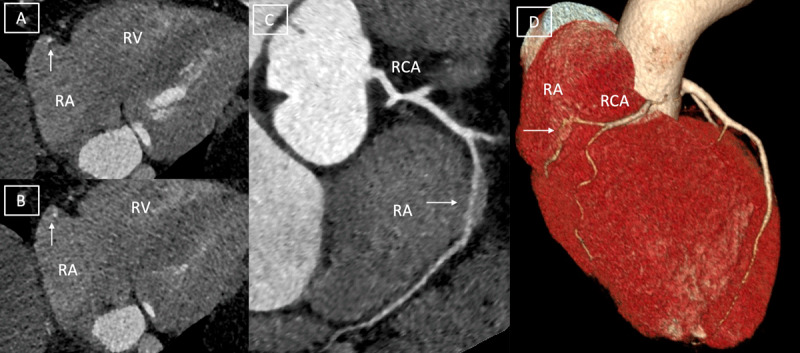

We describe a case of a 59-year-old male who presented with intermittent episodes of atypical chest pain where computed tomography revealed intracavitary course of right coronary artery.The recognition of intra-atrial course of RCA is important as it can predispose patients to inadvertent iatrogenic injuries during surgical or endovascular procedures that can prove catastrophic, even fatal.